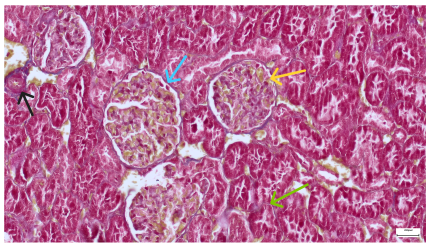

| 4.1. Hematoxylin and Eosin stain, 200× magnification. Normal aspect of the glomerulus, afferent arteriole, efferent arteriole, and normal renal tubules. Control group specimens. | 4.2. Hematoxylin and Eosin stain, 200× magnification. Normal aspect of the juxtaglomerular apparatus. Control group specimens. |

| 4.3. Trichrome Masson stain, 100× magnification, 200 microns scale segment. Arteriole thickening (black), glomerular basal membrane thickening (blue), mesangial cell expansion (yellow), proximal renal tubule basal membrane thickening (green). Group II obese High-Fat-Diet-fed specimens. | 4.4. Hematoxylin and Eosin stain, 200× magnification, 100 microns scale segment. Glomerular congestion and mesangial cell expansion. Group II obese High-Fat-Diet-fed specimens. |